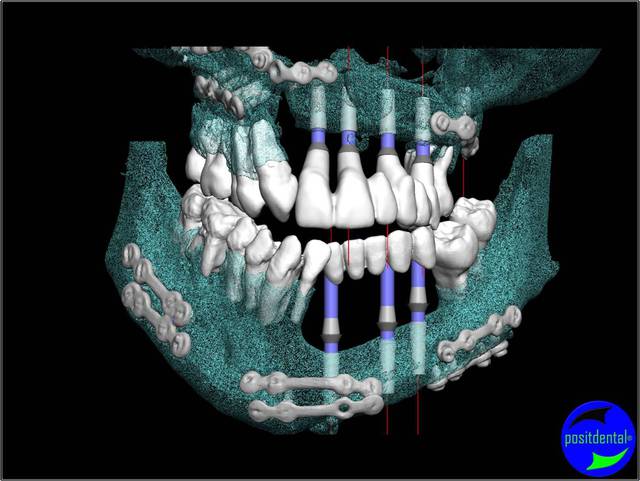

chirurgie à venir

3D maxillaire inférieur et photo

Mci - Eugenol